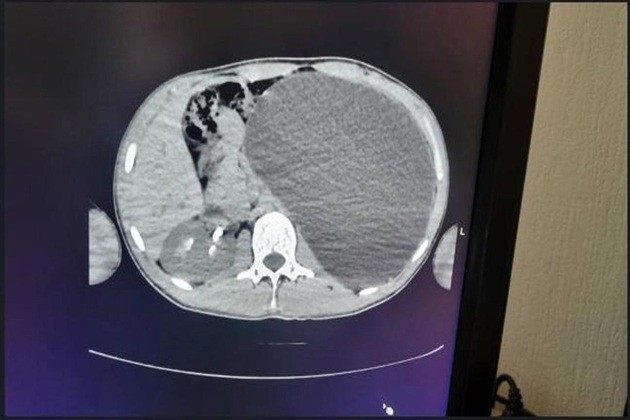

Lo que parecía un simple trámite para conseguir trabajo sirvió para descubrir una amenaza mortal. Un adolescente de 17 años de Novosibirsk, Rusia, se salvó gracias a una ecografía de rutina que reveló que tenía un riñón del tamaño de una botella de cinco litros a punto de estallar, informan las autoridades sanitarias.

El joven, que se sentía completamente sano y nunca había tenido molestias, se sometió a un examen médico obligatorio previo a su contratación. Para su sorpresa, los médicos descubrieron que padecía hidronefrosis, una enfermedad que había inflamado su riñón izquierdo de forma descontrolada. El órgano ocupaba casi todo el abdomen y presionaba el resto de órganos.

«Era una verdadera bomba de relojería», explicaron los especialistas del hospital. «Cualquier traumatismo, cualquier golpe accidental en el abdomen podría haber provocado una ruptura interna». La enfermedad era asintomática y el chico ignoraba por completo el peligro.

Los cirujanos actuaron de inmediato. Mediante una operación de mínima invasión, drenaron el líquido acumulado y extrajeron el órgano dañado. La intervención fue exitosa y el joven se recupera favorablemente. Una vez recibida el alta, podrá por fin incorporarse a su nuevo trabajo.